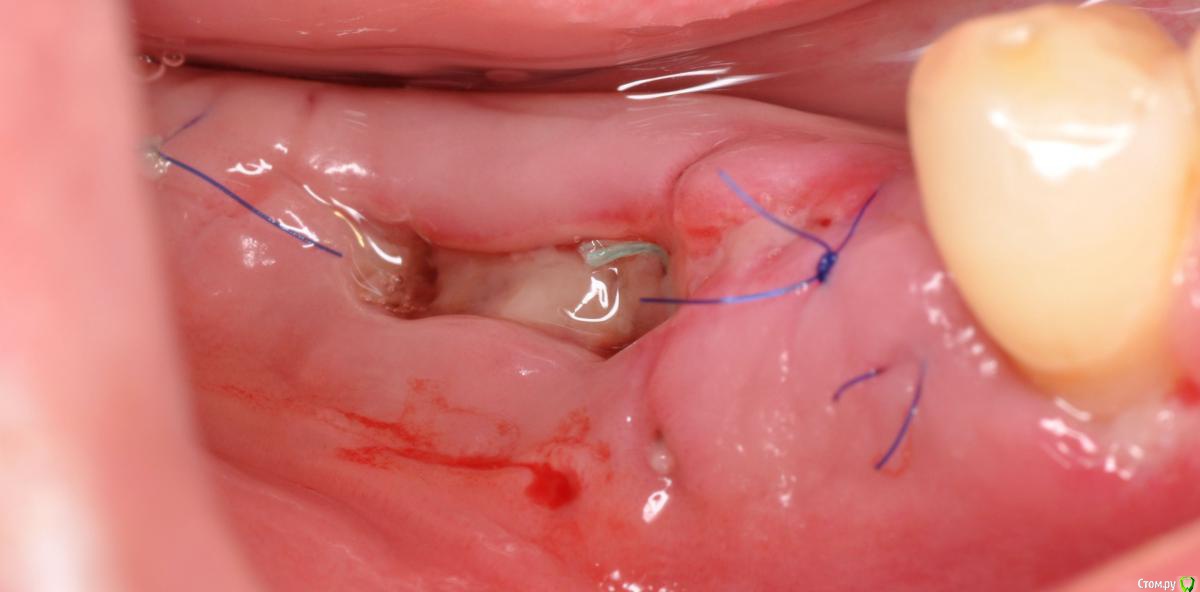

kriokov Опубликовано 23 ноября, 2015 Поделиться Опубликовано 23 ноября, 2015 а через пол года я этим Фторэксом ботинок себе заштопал на работе!) добраться до дома должно хватитьфторэкс в сравнении с унифлекс сразу в день вмешательствачерез 2 сутокчерез 8 суток фторэкс надулся и весь в дерьмецеснял фторэкс, дырки после него на раневой здоровыеснял все, слизистая как после дратвы где был фторэкс Ссылка на комментарий